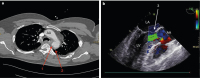

Abbildung 1: 1a: Trauma-CT: AA – Aorta ascendens; 1 – Pseudoaneurysma in loco typico; 2 – beginnendes mediastinales Hämatom, 1b: TEE während TEVAR: LA – linker Vorhof; LV – linker Ventrikel; AA – Aorta ascendens; 3 – hochgradige Aortenklappeninsuffizienz